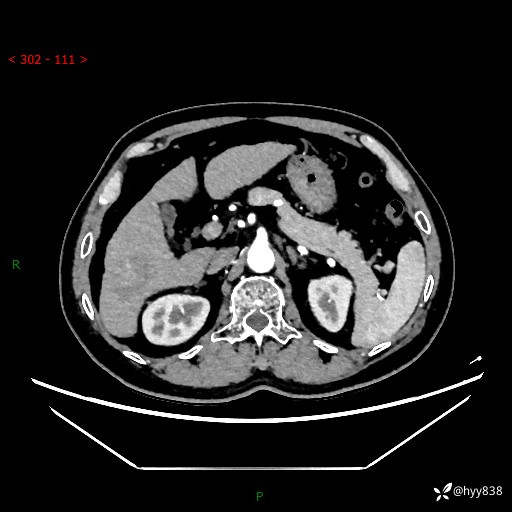

肝脏CT平扫